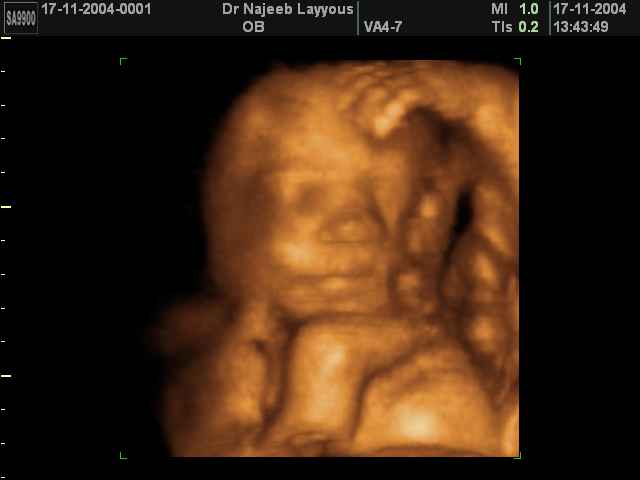

صور لتصرفات الجنين داخل الرحم بجهاز الالتراساوند ثلاثي الأبعاد | الدكتور نجيب ليوس

صور بجهاز الموجات فوق صوتية ثلاثي الأبعاد لتصرفات الجنين داخل الرحم